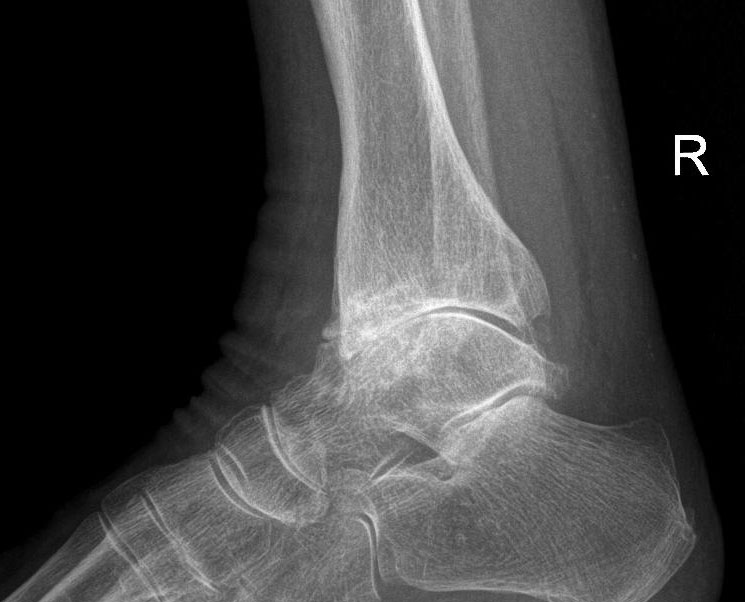

• Fracture of the tibia or fibula

• Talar dome fracture: fracture to the bone inside the ankle joint

• Osteoarthritis: degeneration of the cartilage which lines the bones in the joint